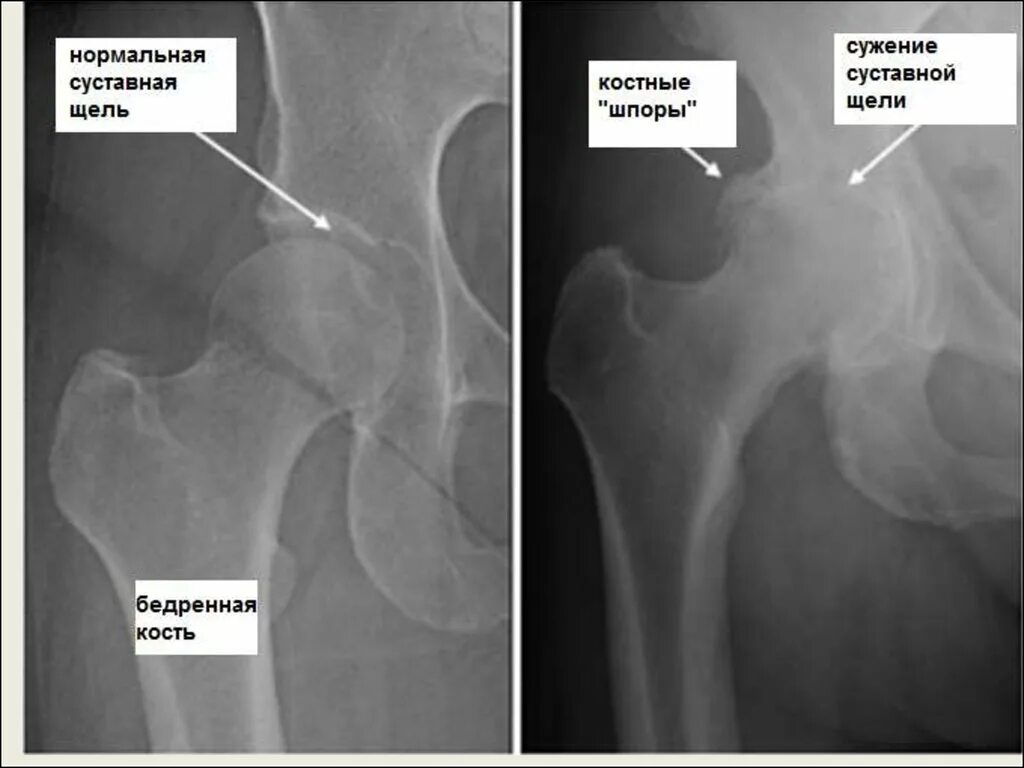

Доа тазобедренных суставов 1 степени что это